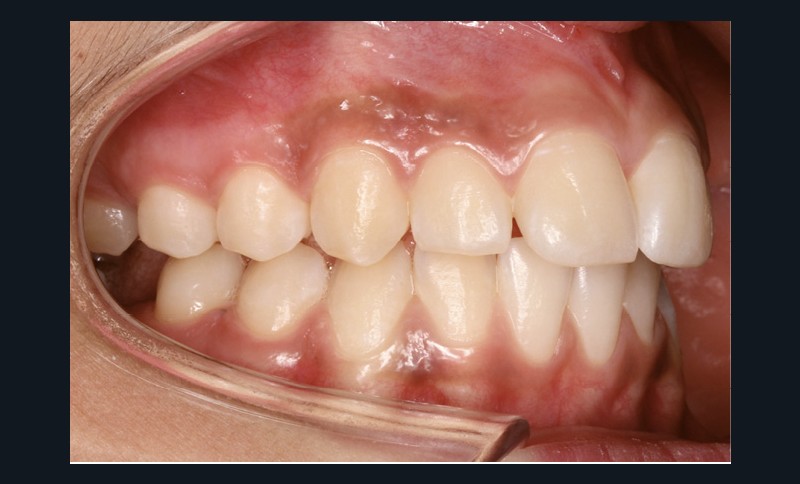

Examen endobuccal (fig. 2a-e)

L’hygiène est satisfaisante et le parodonte sain. On note aux deux arcades l’absence des premières molaires et la fermeture partielle des espaces d’extraction avec mésiorotation marquée de 17, 27 et 37. À la mandibule, l’encombrement antérieur est estimé à 2 mm et les espaces d’extraction résiduels à 12 mm.

Dans le sens transversal, malgré une occlusion correcte des secteurs latéraux, on observe une endoalvéolie maxillaire et une non-concordance des médianes incisives avec déviation de la médiane mandibulaire vers la droite. Le recouvrement incisif est normal.